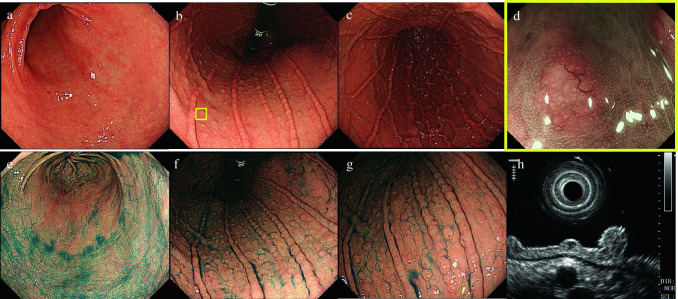

A 53-year-old woman visited a doctor and mainly complained of chest discomfort after meals. Esophagogastroduodenoscopy (EGD) showed multiple granular elevations in the gastric body. She was referred to our hospital for further examination. Her abdomen was flat and soft with no abnormal physical findings. Her medical history included angina and endometriosis, and she owned a pet cat, which is known to be a natural host for NHPH. Blood tests revealed no significant results. EGD showed closed-type atrophic changes in the background mucosa, with multiple granular elevations measuring 2–3 mm centered in the gastric body (Fig. 1a-c, e–g). A small depression was present at the tip of the elevations. Magnified narrow-band imaging showed dendritic dilated blood vessels on the surface layers of all elevations (Fig. 1d). In ultrasonic endoscopy, the lesions were extracted as hypoechoic masses in the shallow part of the second layer (Fig. 1h). Biopsies obtained from multiple elevations showed invasion of atypical cells and some scattered lymphoepithelial lesions and small-to-medium lymphocytes with mild nuclear constriction, even in the lamina propria (Fig. 2a, b). No lymphoma cell infiltration was observed in biopsy tissue from the background mucosa. Immunohistochemical analysis showed that the lesions were positive for CD20 (Fig. 2c), CD79a, and bcl-2 and negative for CD10 and cyclinD1. B-cell markers predominated the stain images, and the patient was diagnosed with MALT lymphoma. Fluorescence in situ hybridization (FISH) showed negative results for the API2-MALT1 gene (Fig. 2e), and IgH gene rearrangement detected a single peak in four out of five areas (Fig. 2f). The urea breath test did not show a high level (approximately 2.2‰) although serum H. pylori IgG antibodies were positive and H. pylori antigen was found in her stool. Because she lived with a cat and her endoscopic findings were atypical for gastric MALT lymphoma, we suspected NHPH infection. Polymerase chain reaction (PCR) was performed using biopsy specimens for H. pylori and five strains of NHPH (H. suis, H. bizzozeroni, H. salmonis, H. felis, H. heilmannii) that typically infect humans (Table 1) [3], and H. pylori and H. suis were detected (Fig. 2g). Gimenez staining of the biopsy tissue did show helical bacilli; however, differences from H. pylori were histologically indistinct, and it was difficult to make a definitive histopathological diagnosis of the NHPH (Fig. 2d). No lesions outside the stomach were found in colonoscopy, small bowel capsule endoscopy, and positron emission tomography–computed tomography. The patient was diagnosed with stage I lymphoma as per the international Lugano classification [4]. Primary treatment involved 7-day bacterial eradication therapy using three oral agents: vonoprazan fumarate, amoxicillin hydrate, and clarithromycin. Subsequently, her stool tested negative for H. pylori antigen, and the bacterial eradication therapy was considered successful. Endoscopic images at 6 months after bacterial eradication showed that multiple granular elevations remained in the gastric body; however, the dilated blood vessels found in the surface layer had disappeared (Fig. 3a–c). Histopathologically, no lymphoma cells remained (Fig. 3d, e). PCR with gastric mucosal tissue after the bacterial eradication treatment confirmed that H. pylori and H. suis had been successfully eradicated (Fig. 3f). Follow-up observation with regular endoscopic examination was planned to check for the recurrence of gastric MALT lymphoma or any changes in the form of the granular elevations.

Fig. 1.

EGD at first visit (before bacterial eradication). a Inconspicuous granular elevations can be seen in the vestibular area, b, c with multiple granular elevations in the body. d Narrow-band-imaging shows dilated blood vessels at the surface layer of the elevations. e Spraying of indigo carmine shows no elevations in the vestibular area. f, g Highly distinct granular elevations can be seen in the body. h In endoscopic ultrasonography, the lesions are extracted as hypoechoic masses on the surface of the second layer. EGD esophagogastroduodenoscopy